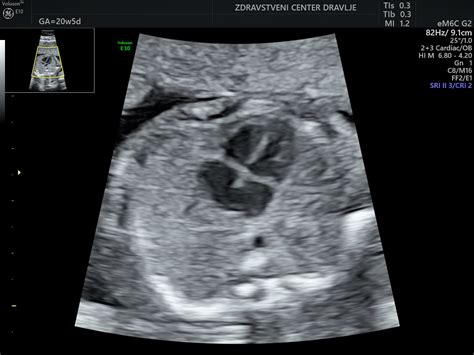

Če še niste obiskali zdravnika, se dogovorite za termin, da lahko začnete načrtovati predporodno varstvo, vključno s prvim ultrazvočnim pregledom, ki se običajno opravi med 8. in 14. tednom. Pri ultrazvočnem pregledu se s pomočjo neškodljivih zvočnih valov izriše natančna slika vašega otroka v maternici. Med 11. in 14. tednom nosečnosti se priporoča tudi pregled nuhalne svetline.